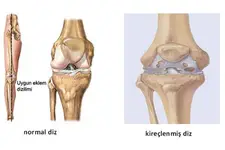

Kıkırdak Doku ve Hastalıklar Kıkırdak dokunun sağlık durumu, birçok hastalığın gelişiminde önemli bir rol oynamaktadır. Osteoartrit gibi dejeneratif hastalıklar, kıkırdak dokusunun bozulmasıyla ilişkilidir. Ayrıca, kıkırdak dokunun yaralanmaları, spor yaralanmaları ve travmalar sonucunda meydana gelebilmektedir. Kıkırdak Doku Araştırmaları ve Gelecek Perspektifleri Günümüzde kıkırdak doku araştırmaları, doku mühendisliği ve yenileyici tıp alanında yoğunlaşmaktadır. Kıkırdak hasarını onarmak veya yeniden oluşturmak amacıyla hücresel tedavi yöntemleri ve biyomühendislik uygulamaları geliştirilmektedir. Bu alandaki ilerlemeler, kıkırdak ile ilgili hastalıkların tedavisinde önemli yenilikler getirebilir. Sonuç olarak, kıkırdak doku, vücutta önemli bir rol oynamakta olup, farklı türleriyle birlikte çeşitli işlevler üstlenmektedir. Bu yapıların sağlığı, genel sağlık durumu üzerinde önemli bir etkiye sahiptir ve araştırmalar bu alanda devam etmektedir. |

Kıkırdak dokunun kendini yenileme özelliğinin az olması, maalesef eklem sağlığı açısından ciddi sorunlar yaratabilir. Kıkırdak dokusu, eklemlerimizin düzgün hareket etmesini sağlar ve bu dokunun zarar görmesi, ağrı, sertlik ve hareket kısıtlılığı gibi problemlere yol açabilir.

Kıkırdak dokusunun hasar görmesi durumunda uygulanabilecek çeşitli tedavi yöntemleri bulunmaktadır. Bu tedaviler arasında fizik tedavi, ilaç tedavisi (ağrı kesiciler ve anti-inflamatuar ilaçlar), enjeksiyonlar (kortikosteroid veya hyaluronik asit) ve ileri vakalarda cerrahi müdahaleler yer alabilir. Cerrahi tedaviler arasında artroskopi, mikrokırık cerrahisi ve kıkırdak nakli gibi yöntemler bulunur.

Tedavi seçenekleri, kıkırdak hasarının derecesine ve hastanın genel sağlık durumuna göre değişiklik gösterebilir. Bu nedenle, bir ortopedi uzmanına danışarak en uygun tedavi planını belirlemek önemlidir.